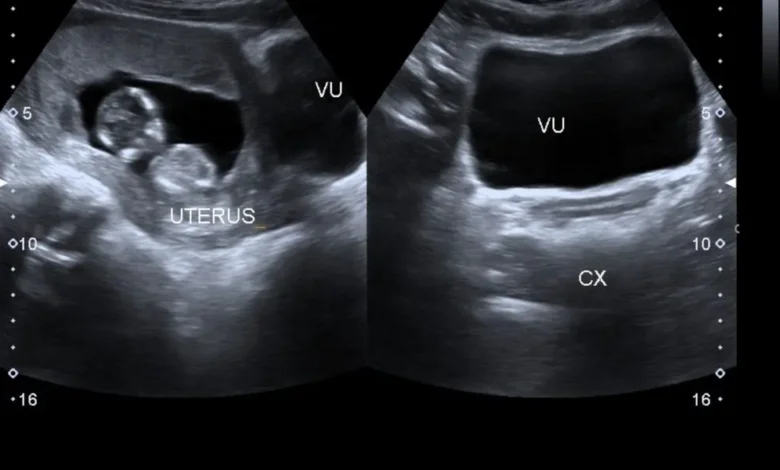

هو كيس مملوء بالسائل يحيط بالجنين خلال فترة الحمل. يُطلق عليه اسم “كيس مح” أو “كيس الصفار”. يختلف حجم كيس الحمل الطبيعي باختلاف عمر الحمل، حيث يتراوح بين 2.5 سم في الأسبوع الخامس إلى 6.5 سم في الأسبوع العاشر.

يُعد الفحص بالموجات فوق الصوتية (السونار) الأداة الرئيسية لمتابعة حجم كيس الحمل. يقوم الطبيب بقياس قطر كيس الحمل بشكل منتظم للتأكد من نموه بشكل طبيعي.